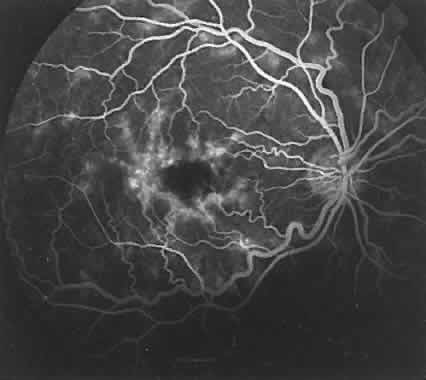

| The abnormal fluorescein pattern is secondary to a disruption of the normal

anatomic relationships of the ocular layers under study. The terms hyperfluorescence and hypofluorescence, relative to the normal pattern and intensity of the fluorescence, describe

any pathologic pattern. Hyperfluorescence may result from (1) the

abnormal presence of fluorescein in a location, (2) a greater-than-normal

concentration of dye in any location where fluorescein is usually

seen, or (3) an increased transmission of fluorescence from an area

of normal dye concentration and distribution due to an overlying pathologic

condition. Hypofluorescence occurs because of (1) the complete absence

of fluorescein in an area where dye is normally found, (2) a relative

decrease from the normal concentration of fluorescein in any particular

area, or (3) a blockage of transmission of the normal fluorescence

secondary to an overlying pathologic condition. HYPERFLUORESCENCE Hyperfluorescence due to accumulation of fluorescein in an area where it is not normally seen is well portrayed in a focal detachment of the RPE (Fig. 18), in which the dye accumulates between the RPE and Bruch's membrane (see Fig. 18A). The RPE appears to be firmly attached to Bruch's membrane, and when fluid accumulates in this area, the RPE delineates itself with sharp, abrupt borders (see Fig. 18B-D). Central serous chorioretinopathy causes an area of hyperfluorescence because of the presence of the dye between the retinal photoreceptor cells and the RPE (Fig. 19). This may be related to a detachment of the RPE and is associated in some way to a defect in the normal mechanism of fluid exchange across the RPE between the choroid and the sensory retina. The attachment of the photoreceptors to the RPE may not be as strong as the attachment of the RPE to Bruch's membrane. This may be why the borders of fluorescence in the secondary serous retinal detachments found in central serous chorioretinopathy are more diffuse (see Fig. 19B) than those in a detachment of the RPE (see Fig. 18B). Ocular histoplasmosis may also show choroidal hyperfluorescence because of the abnormal presence of a choroidal neovascular membrane forming a nodular elevation of the RPE (Fig. 20A and B). In the early stage of this disorder, when a neovascular tuft is clearly seen, the very early phases of the fluorescein study clearly show the new vessels filling with fluorescein. In the later phases, dye leaks from the vessels to fill the surrounding tissue and may even cause staining of the RPE (see Fig. 20C-E). Hyperfluorescence is also caused by an increased concentration of fluorescein in an area of the uveal tract, where it is normally seen in the intravascular and extravascular components of the choroidal stroma. A choroidal hemangioma shows hyperfluorescence very early in the study (Fig. 21A and C). This vascular tumor and the choroidal vasculature fill with dye at the same time. For this reason, these lesions often reach a peak of hyperfluorescence in the early phases of the fluorescein study. Even though there is leakage and staining of the extravascular components, because these are highly vascular tumors, the peak of the hyperfluorescence may diminish before the late phases of the study (see Fig. 21D and E). Hyperfluorescence from a solid tumor (e.g., a choroidal melanoma or metastatic lesion; Figs. 22 and 23) also is caused by an increased accumulation of fluorescein in the uveal stroma at the tumor site. These masses are usually associated with increased vascularity and therefore increased fluorescence. Fluorescein leaks rapidly into the extravascular space to fill the stroma of these tumors (see Figs. 22A and 23A). Because these are solid tumors of densely packed cells, it probably takes time for the fluorescein to completely penetrate the extravascular space of the tumor. Lesions of this nature may show a delay in the hyperfluorescent peaks as compared with choroidal hemangiomas, and for the same reason may fluoresce longer. Hyperfluorescence, as seen with the previously mentioned tumors, also results from transmission through pigment epithelial defects and from the presence of fluorescein in cystic spaces within the retina. Hyperfluorescence may also be caused by the transmission of normal background choroidal fluorescence through defects of the RPE secondary to various pathologic conditions. In albinism, a defect in production of melanosomes leads to increased transmission of choroidal fluorescence through the nonpigmented RPE (see Fig. 17). With degenerative disease affecting the RPE, focal areas lacking pigment are seen with adjacent areas of hyperpigmentation. In the early phases of a fluorescein study, the choroidal fluorescence is transmitted through these defects in the RPE,43 whereas in the late phases, there is actual staining with fluorescein in these areas (Fig. 24). The adjacent focal areas of hyperpigmentation cause blockage of the background choroidal fluorescence. Drusen may act in the same manner because the RPE may be thinned over these lesions.44 Transmission of the choroidal fluorescence occurs early, whereas actual staining with the dye is seen late (Fig. 25). HYPOFLUORESCENCE Hypofluorescence from absence of fluorescein in an area where it would normally be seen may be secondary to a lack of perfusion or to absence of the tissue. The hypofluorescence seen in the early frames of an individual with a coloboma results from the absence of the choriocapillaris; even though the RPE is absent, there is only transmission of the large choroidal fluorescein-filled vessels (Fig. 26A and B). In the very late stages of the study, the coloboma hyperfluoresces secondary to scleral staining in the area devoid of RPE (see Fig. 26C and D). Hypofluorescence can also be secondary to a relative decrease in the fluorescein concentration. This may partially explain why a choroidal nevus does not fluoresce (Fig. 27). In addition to the nevus cells occupying space where the dye would normally accumulate, hypofluorescence is also caused by obscuration of fluorescence by the heavy concentration of pigment (Fig. 28). (Obscuration or blockage of choroidal fluorescence as a mechanism of hypofluorescence may be seen in several other conditions. A hemorrhage under the RPE causes a corresponding area of hypofluorescence due to a blockage of the underlying fluorescence (Fig. 29). For the same reason, an area of hypertrophy of the RPE will appear hypofluorescent (see Fig. 28). In addition, patients with Stargardt's disease often exhibit a silent choroid secondary to blockage of background choroidal fluorescence by lipofuscin accumulation in the RPE (Fig. 30).

In patients with choroidal folds, there are alternating areas of hypofluorescence and hyperfluorescence (Fig. 31).45 The hypofluorescent lines correspond to the areas between the peaks of the folds where the RPE pigment concentration is greatest, causing a relative blockage of the underlying fluorescence. The alternating hyperfluorescent lines represent the peaks of the folds where the pigment concentration is less, allowing a greater transmission of the choroidal fluorescence. |